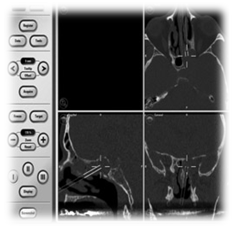

Sphenoid sinus mucocele compromises 1–2% of all paranasal sinuses mucoceles.6 The pathophysiology of mucocele is retention of mucoid secretion within the sinus, leading to thinning, distension and erosion of the sinus bony walls. The most common location is the frontal sinus then the anterior ethmoidal sinus .Sphenoid sinus mucocele can be presented with headache, visual disturbance due to optic or oculomotor, trochlear and abducent nerves involvement, diplopia, and external ophthalmoplegia. A rare clinical entity, mucocoeles seem to be more common in patients with a history of radiation to the head and neck.30 reported up to 30% of patients with isolated sphenoid mucocoeles had a history of previous radiation. Diagnosis of sphenoid sinus mucocele is mainly by CT scan (Figure 7) of that would show a low attenuation on CT. MRI scan (Figure 8) is important to detect the extension of the mucocele and that would show a low signal on T1 and a high signal on T2. Asymptomatic mucocele can be leave without any surgical intervention. Surgical intervention is required when it is symptomatic, or if it is presented with complications like orbital or cranial involvement. Surgical treatment of sphenoid mucocele is by endoscopic transnasal image-guided sphenoidotomy (Figure 9) the aim of surgery is to do wide sphenoidotomy to allow adequate drainage and to avoid recurrences of the disease (Figure 10). Marsupialization of the mucocele is another option with good results.

Image guided endoscopic surgery for marsupilisation of left sphenoid mucocele

Figure 7 CT scan left sphenoid mucocele.

Figure 8 MRI, left sphenoid mucocele.

Figure 9 Image-guided surgery IGS.